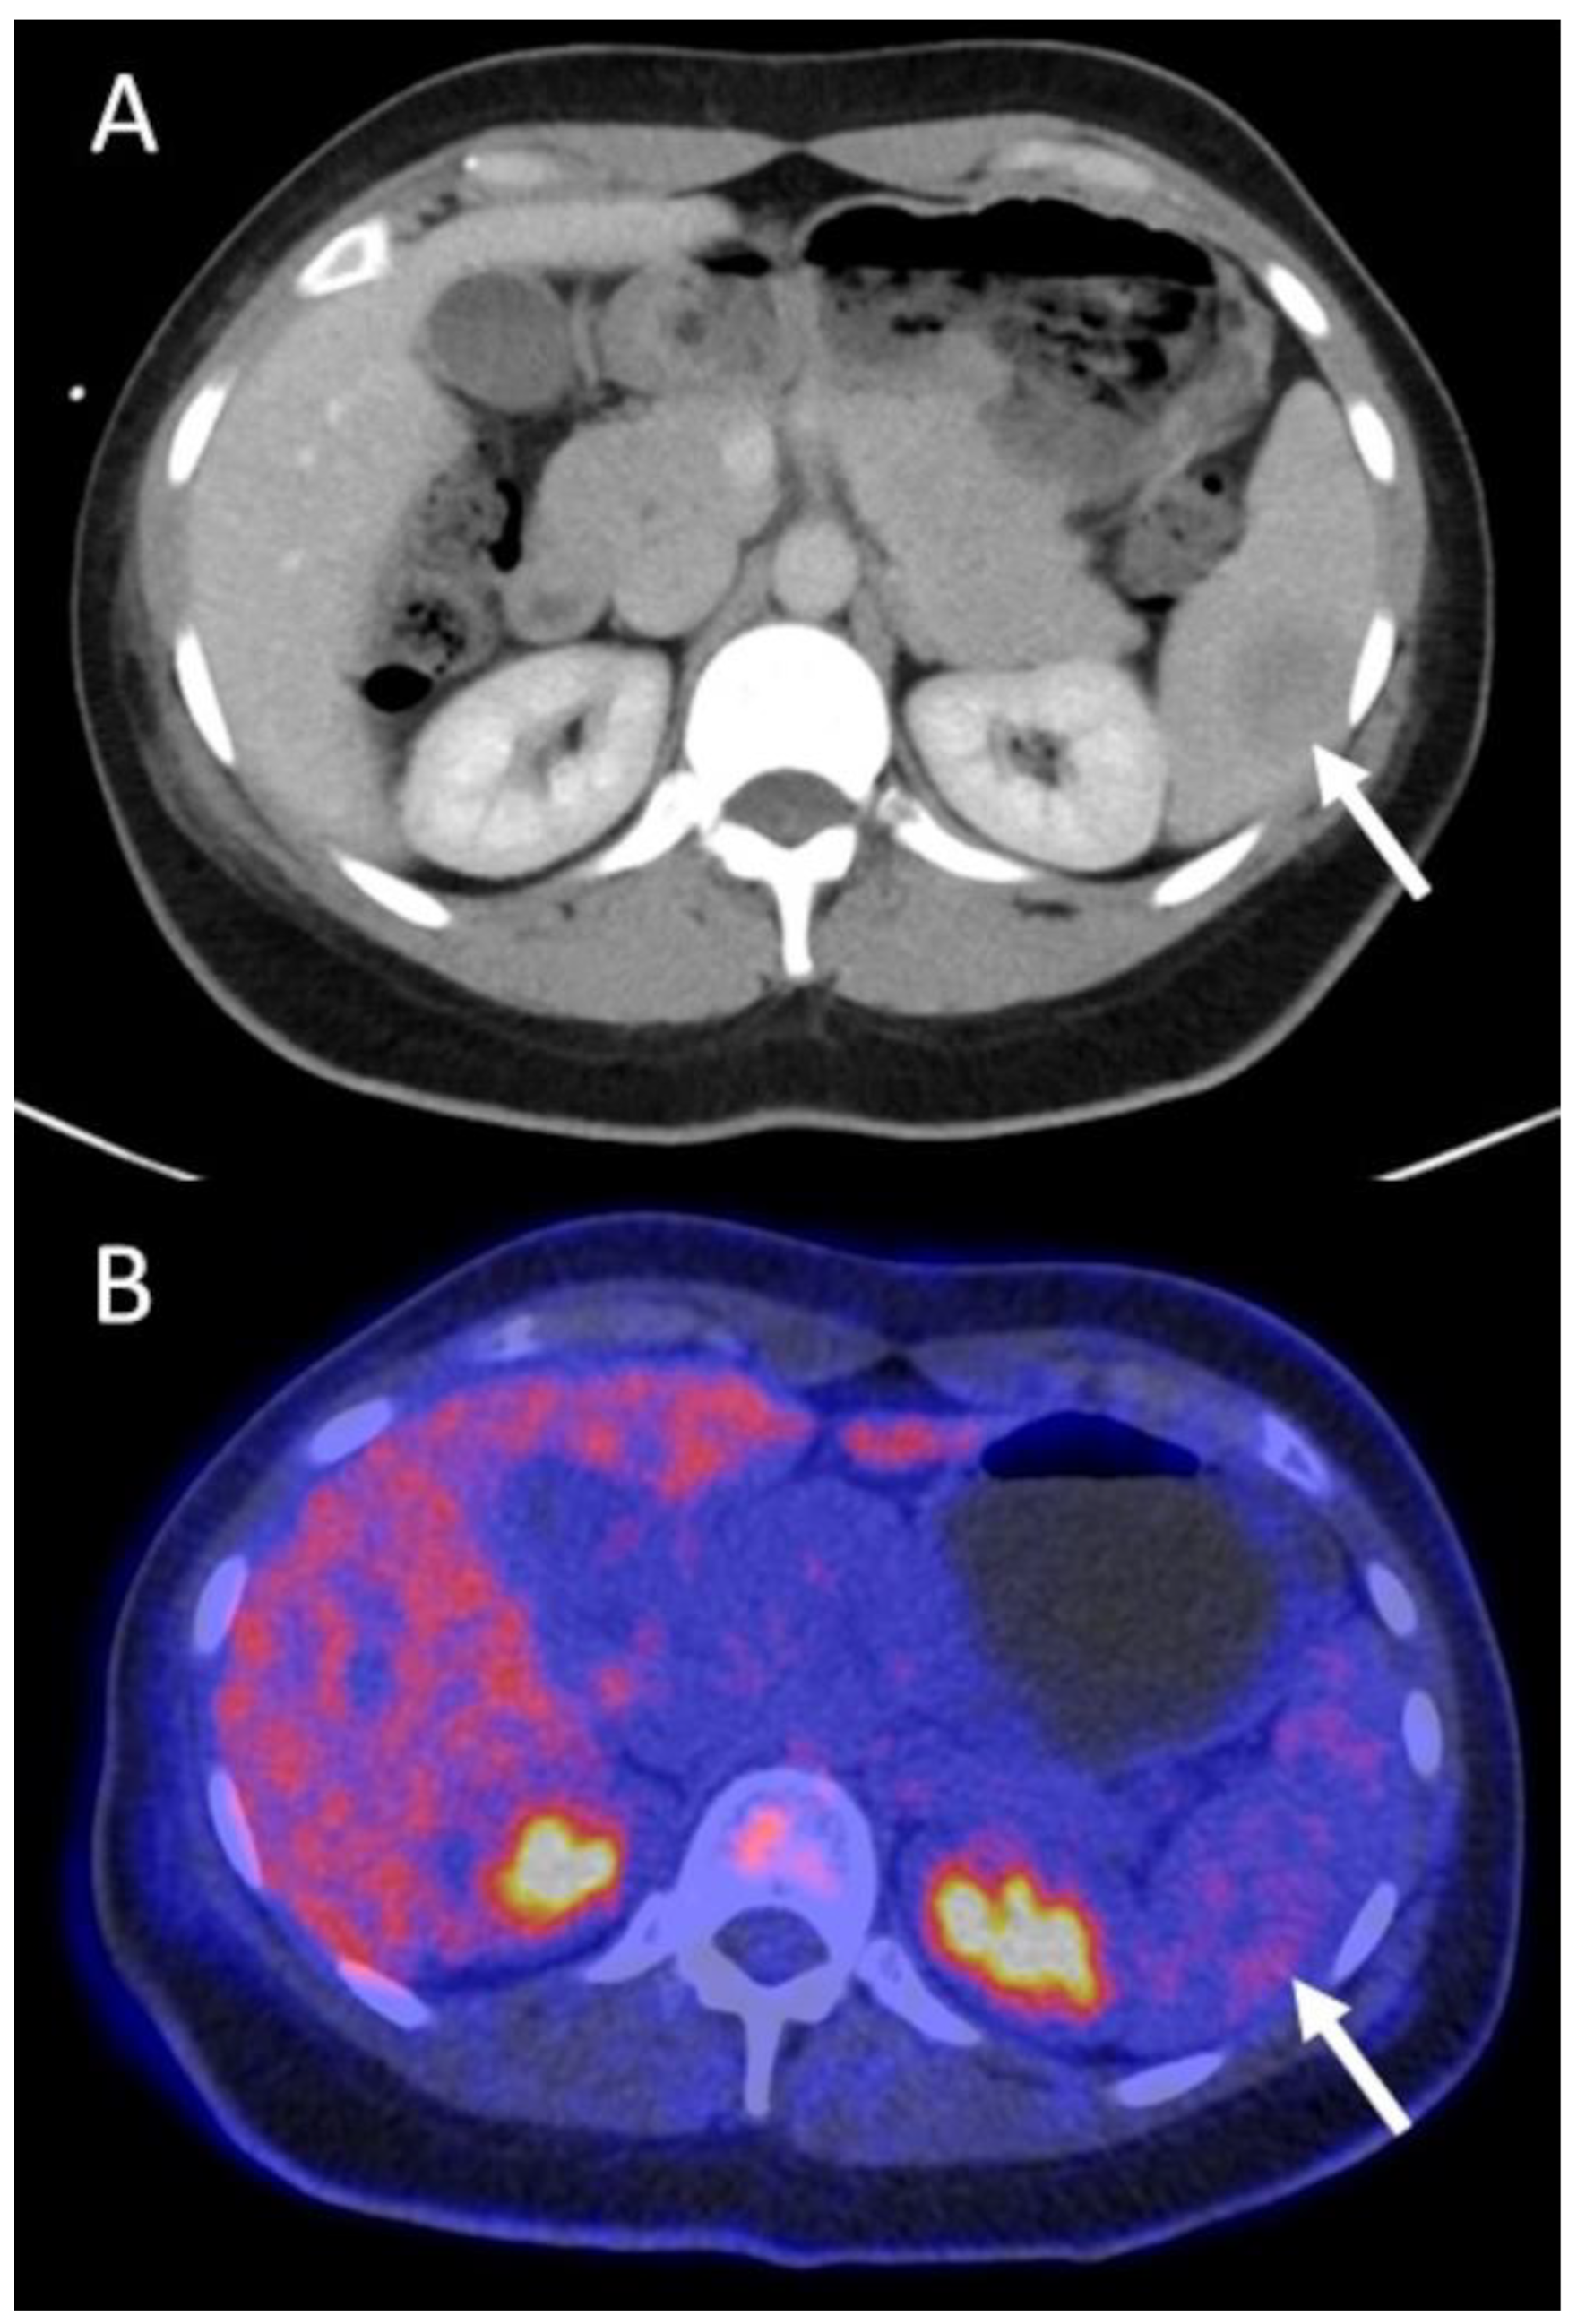

3.4.2. Restaging Patients (n = 17/52)

| Group B Restaging (n = 17 scans in 13 patients) | Stage I: n = 3 Stage II: n = 5 Stage III: n = 2 Stage IV: n = 3 | non-treatment | systemic | C | P | progressive disease | yes, not specified | 1 | Major (n = 3) | earlier therapy start with improved outcome, avoidance of additional tests |

| systemic | non-treatment | P | P | complete remission | no | 1 | ending of therapy and preventing its side effects | |||

| systemic | systemic + RTX | P | P | progressive disease | no | 1 | earlier therapy start with improved outcome | |||

| systemic | systemic (modified) | P | P | progressive disease | yes, invasive | 2 | Minor (n = 11) | better customized therapy/early replacement of ineffective therapy, avoidance of invasive tests | ||

| yes, not specified | 1 | better customized therapy/early replacement of ineffective therapy, avoidance of additional tests | ||||||||

| no | 5 | better customized therapy/early replacement of ineffective therapy | ||||||||

| surgery + systemic | surgery + systemic | C | C | partial remission | yes, invasive | 1 | avoidance of invasive tests | |||

| systemic | systemic | P | P | stable disease | yes, invasive | 1 | avoidance of invasive tests | |||

| mixed | yes, not specified | 1 | avoidance of additional tests | |||||||